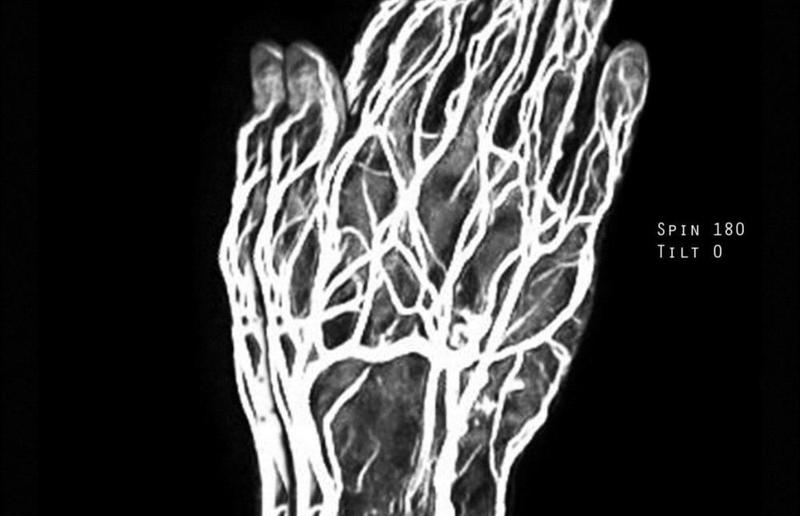

Igor F. Petkovic "xray pray"

Grundlage des Projektes ist die Hinterfragung geistig-geistlicher Inhalte durch wissenschaftliche bildgebende Verfahren mit den Mitteln der Kunst. Durch das Verfahren des Röntgens und/oder der Magnetresonanztomographie werden menschliche (körperliche) Haltungen des Glaubens, des Betens und des Meditierens durchleuchtet und abgebildet. Zur Disposition stehen Fragen wie: Kann man Gott "scannen"? "Sieht" man Glaube? Was verbergen gefaltete, betende Hände? Das Projekt ist ein Kooperationsprojekt mit der Theologischen Fakultät der KFUniversität Graz und der Klinischen Abteilung für allgemeine radiologische Diagnostik der MedUniversität Graz.

gefaltete hände, segnende hände, hände beim sich bekreuzen, mit rosenkranz,..

kann man gott "scannen", "sieht" man glaube, was verbergen gefaltete, betende hände?